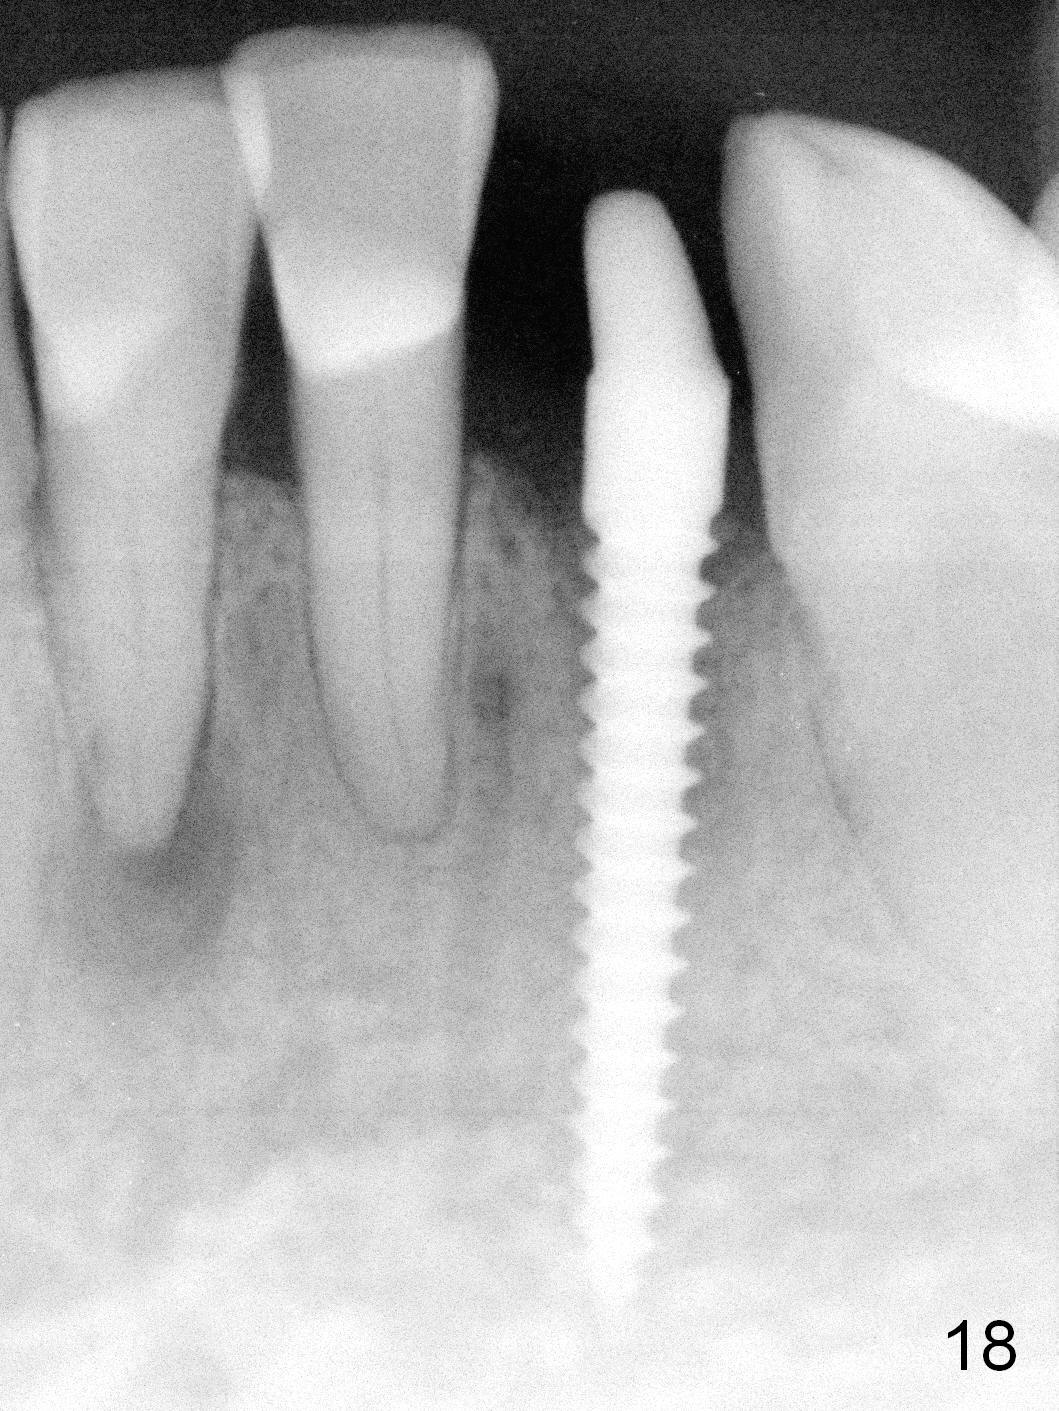

Five months postop, the peri-implant space reduces (Fig.18). A keratinized band forms buccal to the implant (Fig.19 *). The provisional dislodges probably due to the buccal placement (Fig.20).